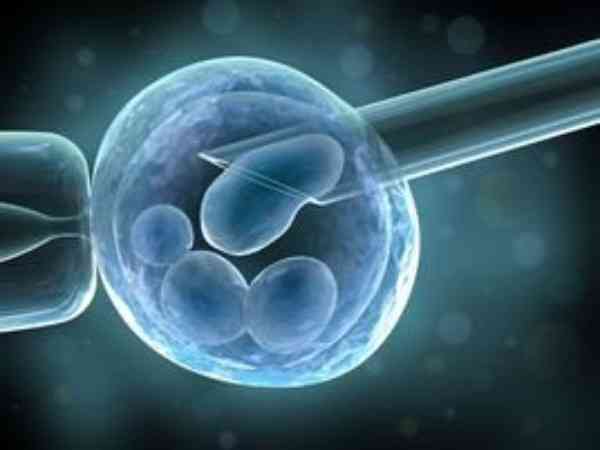

辅助孵化会不会伤害胚胎看过来,确实有一定风险要注意

试管婴儿冻囊胚辅助孵化会伤害到胚胎的风险很小,试管婴儿冻囊胚辅助孵化是指在试管婴儿胚胎移植回女性宫腔前,人为地在透明带上打洞或使透明带变薄,或使透明带溶解消失,以此缩短胚胎着床时间和提高妊娠率。虽然这项技术有着一定的好处,但任何手术都是存在一定风险的,不能保证100%的安全可靠,如试管婴儿冻囊胚辅助孵化如果操作不当,有潜在损伤胚胎的可能,有可能增加单卵双胞胎的风险,甚至出现连体儿的可能,但出现这样风险的情况很小,只要选择正规的医院,就可以规避这样的情况发生。